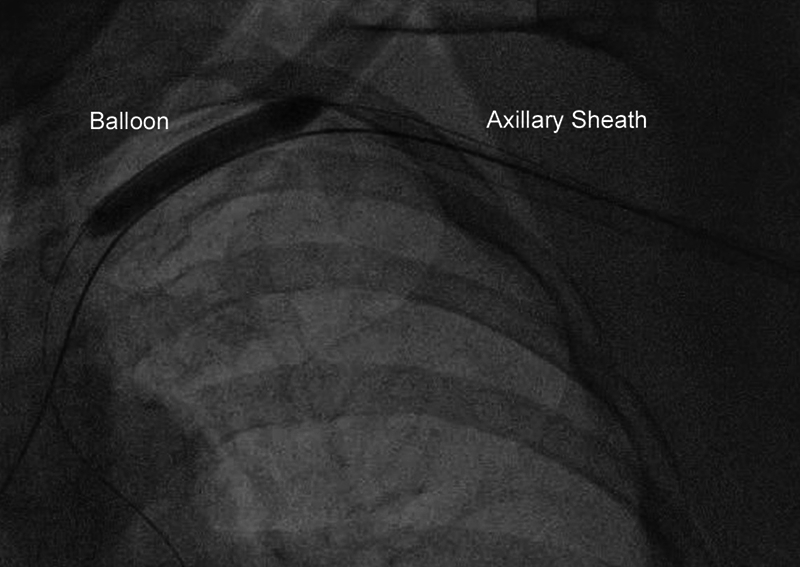

Figure 4.

Dry closure of the axillary artery, using a balloon inserted from the femoral artery and inflated in the subclavian artery before removal of the axillary sheath.